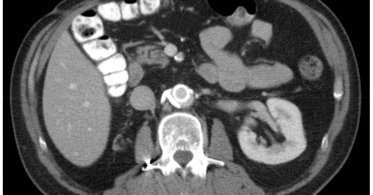

π©»β οΈ Rare trauma complication. This case highlights endovascular repair of a hepatic artery pseudoaneurysm with celiac dissection & intramural hematoma after blunt abdominal trauma, showing the power of minimally invasive management. π https://t.co/F9sOXcp1OU

#VascularTrauma

jvscit.org

Hepatic artery pseudoaneurysm is a concerning yet rare complication of blunt abdominal trauma, with treatment recommended upon diagnosis.1 Endovascular repair of hepatic artery aneurysms has gained...